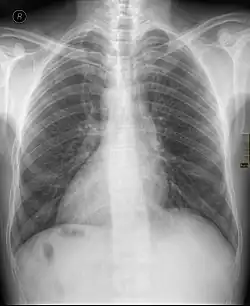

Dextrokardie

Mit dem Begriff Dextrokardie (Rechtsherzigkeit), abgeleitet von altgriechisch δεξιός dexiós, deutsch ‚rechts‘ und altgriechisch καρδία kardía, deutsch ‚Herz‘, wird in der Medizin ein Phänomen bezeichnet, bei dem sich das Herz ständig oder zeitweilig in der überwiegend rechten statt in der linken Brusthöhle befindet.

Eine Dextrokardie kann angeboren im Rahmen eines sogenannten Situs inversus (totalis) auftreten,[1] bei dem im Brustkorb oder auch im ganzen Körper sämtliche Organe spiegelverkehrt angelegt sind. Auch kann Dextrokardie durch eine Herzdrehung entstanden sein, etwa als Folge einer Lungen- oder Brustfellerkrankung.